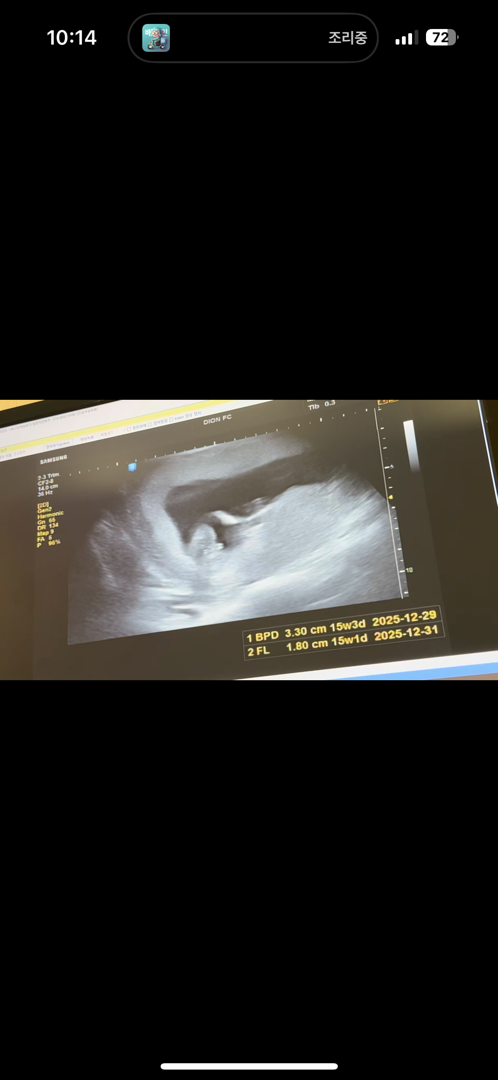

초음파 아들맞죵??ㅎㅎ

ㅎㅎ